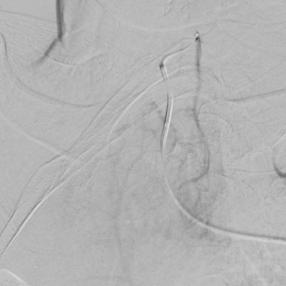

左上肺癌,锁骨上动脉造影,甲状颈干分支供应左上肺癌,反复使用单弯导管无法勾到责任血管,单弯导管热蒸汽成形后成功找到责任血管,微导管超选后CBCT证实肿瘤染色丰富后进行微球栓塞。